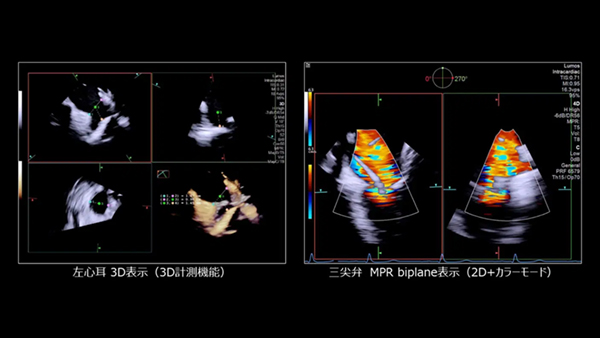

「AcuNav Lumos 4D ICE」は,シーメンスヘルスケアが2024年4月に発売した超音波画像診断装置「ACUSON Origin」と接続して使用することで,3Dの心腔内エコーが可能になる。リアルタイムな3Dエコー画像により,これまで観察が難しかった心血管の解剖学的構造を視覚化する。例えば,心臓の右心房と右心室の間にある三尖弁の疾患の観察や評価は,従来の2Dエコーや経食道エコーでは難しいとされ,三尖弁が経食道エコーで十分に可視化できるのは全症例のおよそ11%とされていた*4が,「AcuNav Lumos 4D ICE」を用いることで,リアルタイム3D表示で右心房から三尖弁の解剖学的構造を明確に視覚化することが可能*5。 また,3Dのカラードプラ表示により,血流の位置や方向,速度を把握することで,心血管の機能評価をサポートする。